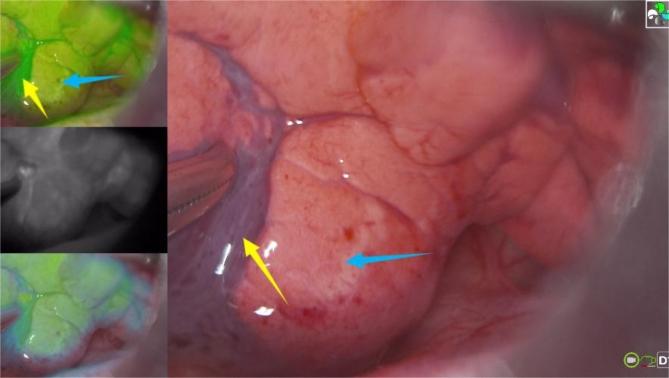

Identification of lesion demarcation during thoracoscopic anatomical lesion resection is fundamental for treating children with congenital lung malformation. Existing lesion demarcations do not always meet the needs of clinical practice. This study aimed to explore the safety and efficacy of near-infrared fluorescence imaging with nebulized inhalation of indocyanine green for thoracoscopic anatomical lesion resection in children with congenital lung malformation. Under the fluorescence scope, the area of uniform green fluorescence was produced when indocyanine green was distributed into normal lung tissue, and lesions showed little or no green fluorescence, thus delineating a clear fluorescent lesion demarcation. Under the guidance of fluorescent demarcation, all the patients except one case of extralobar sequestration underwent thoracoscopic anatomical lesion resection successfully.

在胸腔镜解剖性病变切除术中识别病变边界对于治疗先天性肺发育不良患儿至关重要。现有的病变边界划分并不总能满足临床实践的需求。本研究旨在探讨雾化吸入吲哚菁绿的近红外荧光成像在先天性肺发育不良患儿胸腔镜解剖性病变切除术中的安全性和有效性。在荧光视野下,当吲哚菁绿分布到正常肺组织时会产生均匀的绿色荧光区域,而病变显示很少或没有绿色荧光,从而勾勒出清晰的荧光病变边界。在荧光边界的引导下,除1例肺叶外隔离症患者外,所有患者均成功接受了胸腔镜解剖性病变切除术。